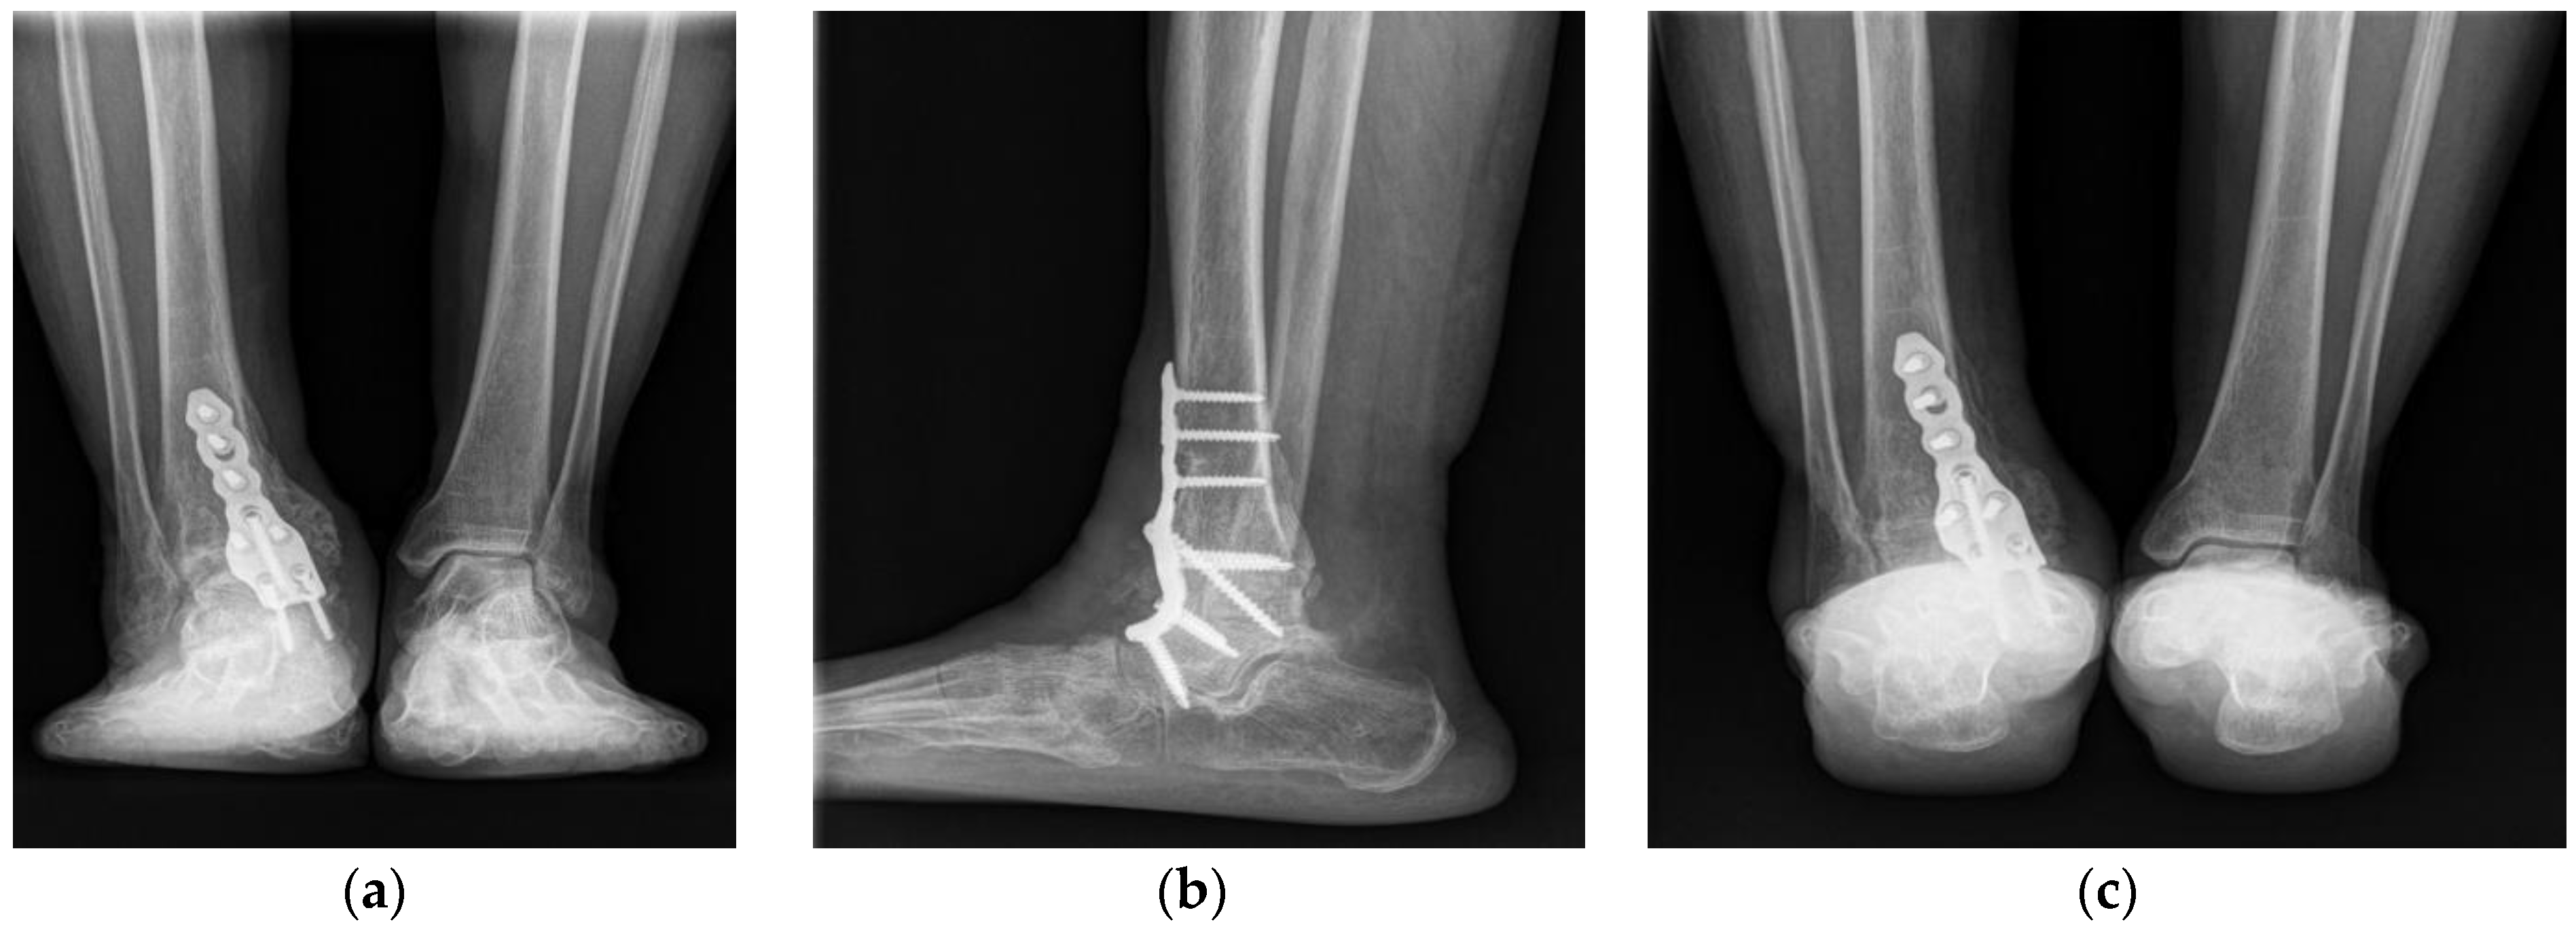

2. Case Presentation